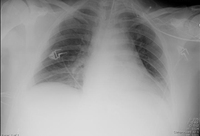

Radiografía de tórax que muestra la hiperinflación en un paciente con EPOC. El tórax distendido es causado por el componente enfisema de la EPOC, en lugar de por la bronquitis crónica, que subyace los síntomas de tos

De la colección personal del Dr. M. A. Sharifabadand, SUNY en Stony Brook School of Medicine, Departamento de Medicina Intensiva y Pulmonar, Mineola, Nueva York y el Dr. J. P. Parsons, The Ohio State University Medical Center, Columbus; usado con autorización